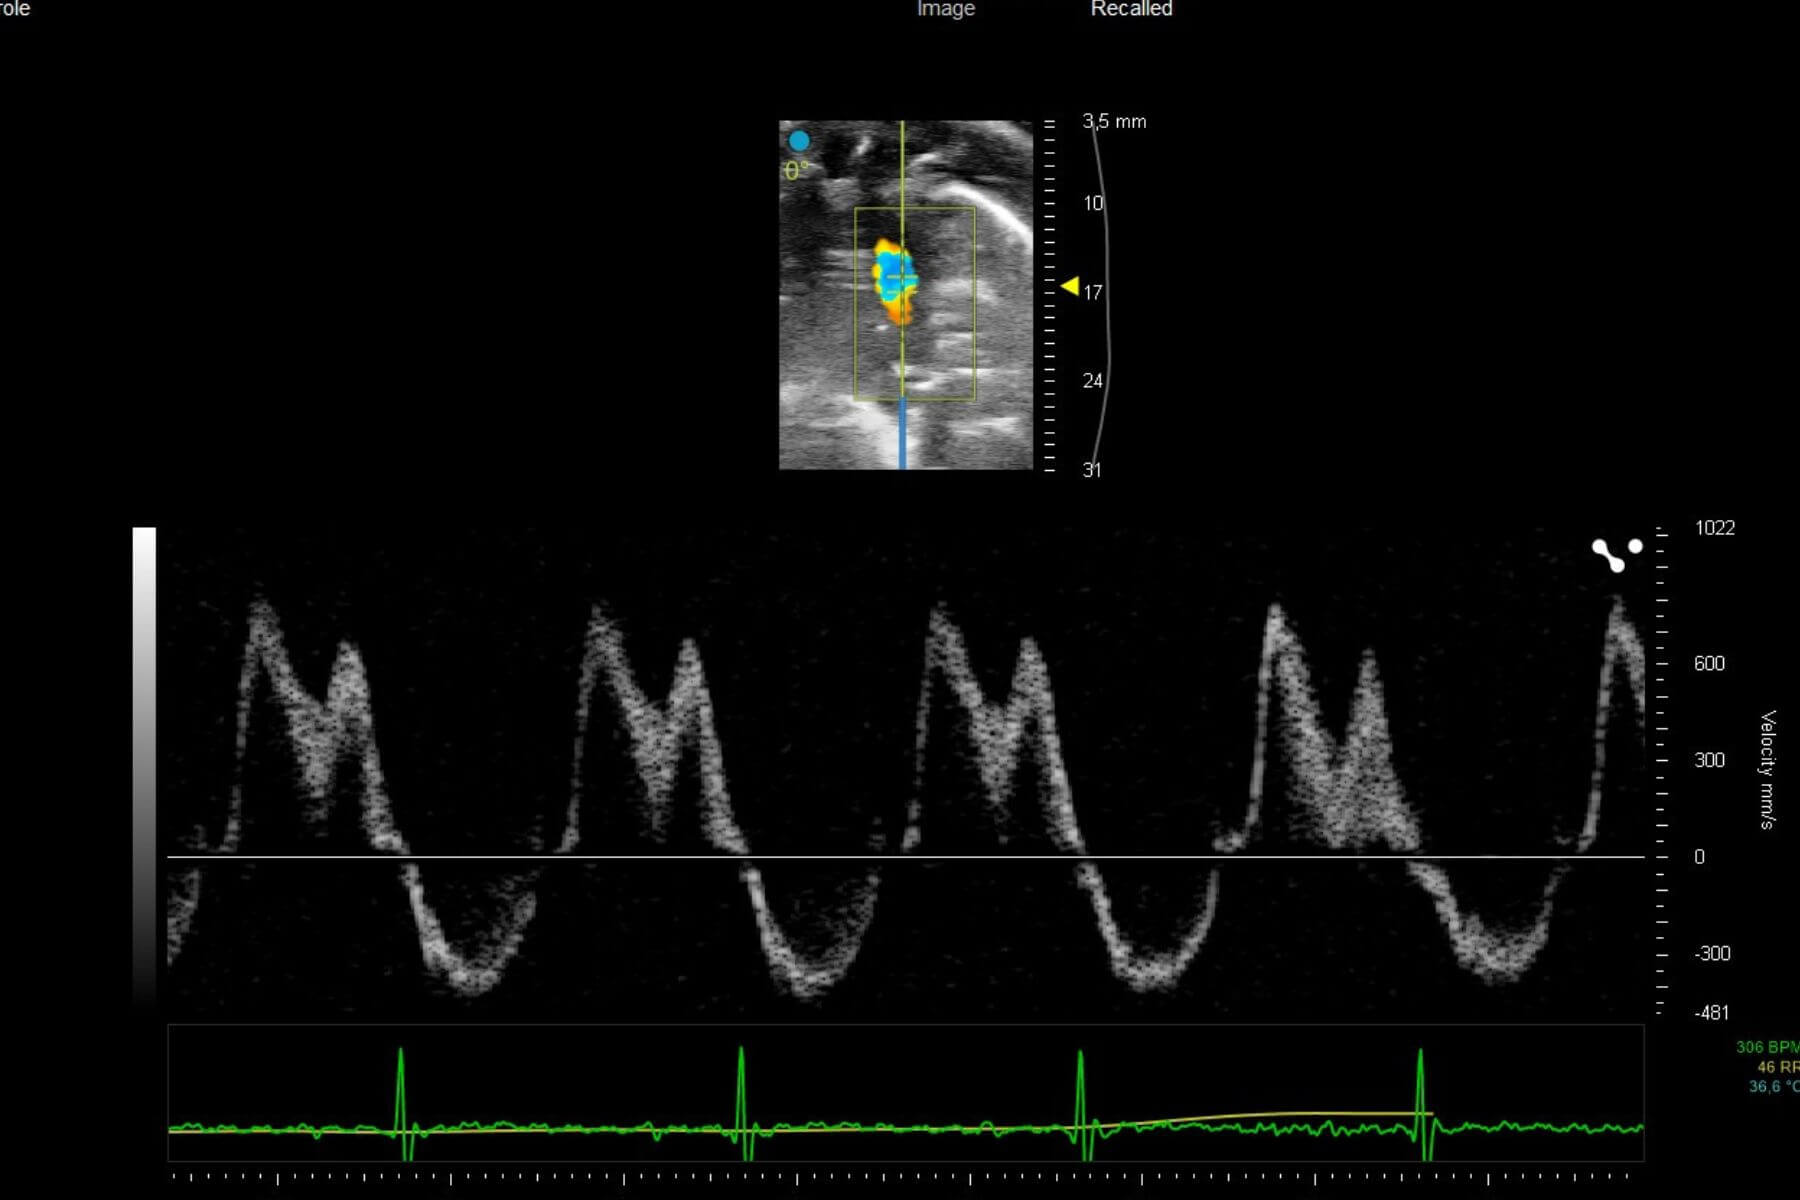

Right heart failure is characterized by the inability of the right ventricle to effectively pump blood toward the lungs. This dysfunction often results from a chronic increase in pressure within the pulmonary artery, as seen in pulmonary arterial hypertension (PAH). Faced with this persistent overload, the right ventricle undergoes remodeling, progressively leading to impaired cardiac function.

Syncrosome’s portfolio enables you to evaluate the effects of your drug candidates in recognized and validated pathological models designed for the pharmacological assessment of cardiac function, as well as cardiac and pulmonary arterial tissue remodeling.

Hypoxia model

The hypoxia model is a classic approach to induce moderate pulmonary arterial hypertension in animals. It relies on the induction of chronic hypoxia using specially designed hypoxia chambers. The model is characterized by persistent pulmonary vasoconstriction, followed by moderate remodeling of the pulmonary arteries.

Sugen-Hypoxia

The SUGEN‑hypoxia model combines the injection of a VEGF receptor inhibitor with prolonged exposure to hypoxia to induce progressive and severe pulmonary hypertension accompanied by right‑ventricular heart failure. This model reproduces most of the clinical features observed in humans, including plexiform lesions in the pulmonary arterioles. It is considered the reference model for studying advanced forms of PAH, allowing the evaluation of therapies targeting complex vascular remodeling, cell proliferation, or endothelial dysfunction. Its severity and stability make it a powerful tool for generating highly translational preclinical data.

Monocrotaline (MCT)

The monocrotaline (MCT) model is one of the most widely used approaches for the experimental induction of PAH. A single injection of MCT causes marked endothelial and inflammatory injuries in the pulmonary arterioles. Mimicking the human disease, the model is characterized by progressive vascular remodeling and right‑ventricular hypertrophy. This quick model is useful for the rapid screening of therapies targeting various key features of PAH. Its well‑characterized kinetic allows optimization of therapeutic windows and the generation of robust data to demonstrate the efficacy of your drug candidates.

Our platform enables the direct evaluation of therapeutic candidates in both HFrEF and HFpEF models, integrating comprehensive assessments of left ventricular function by echocardiography, cardiac remodeling, and cardio-renal-metabolic interactions.